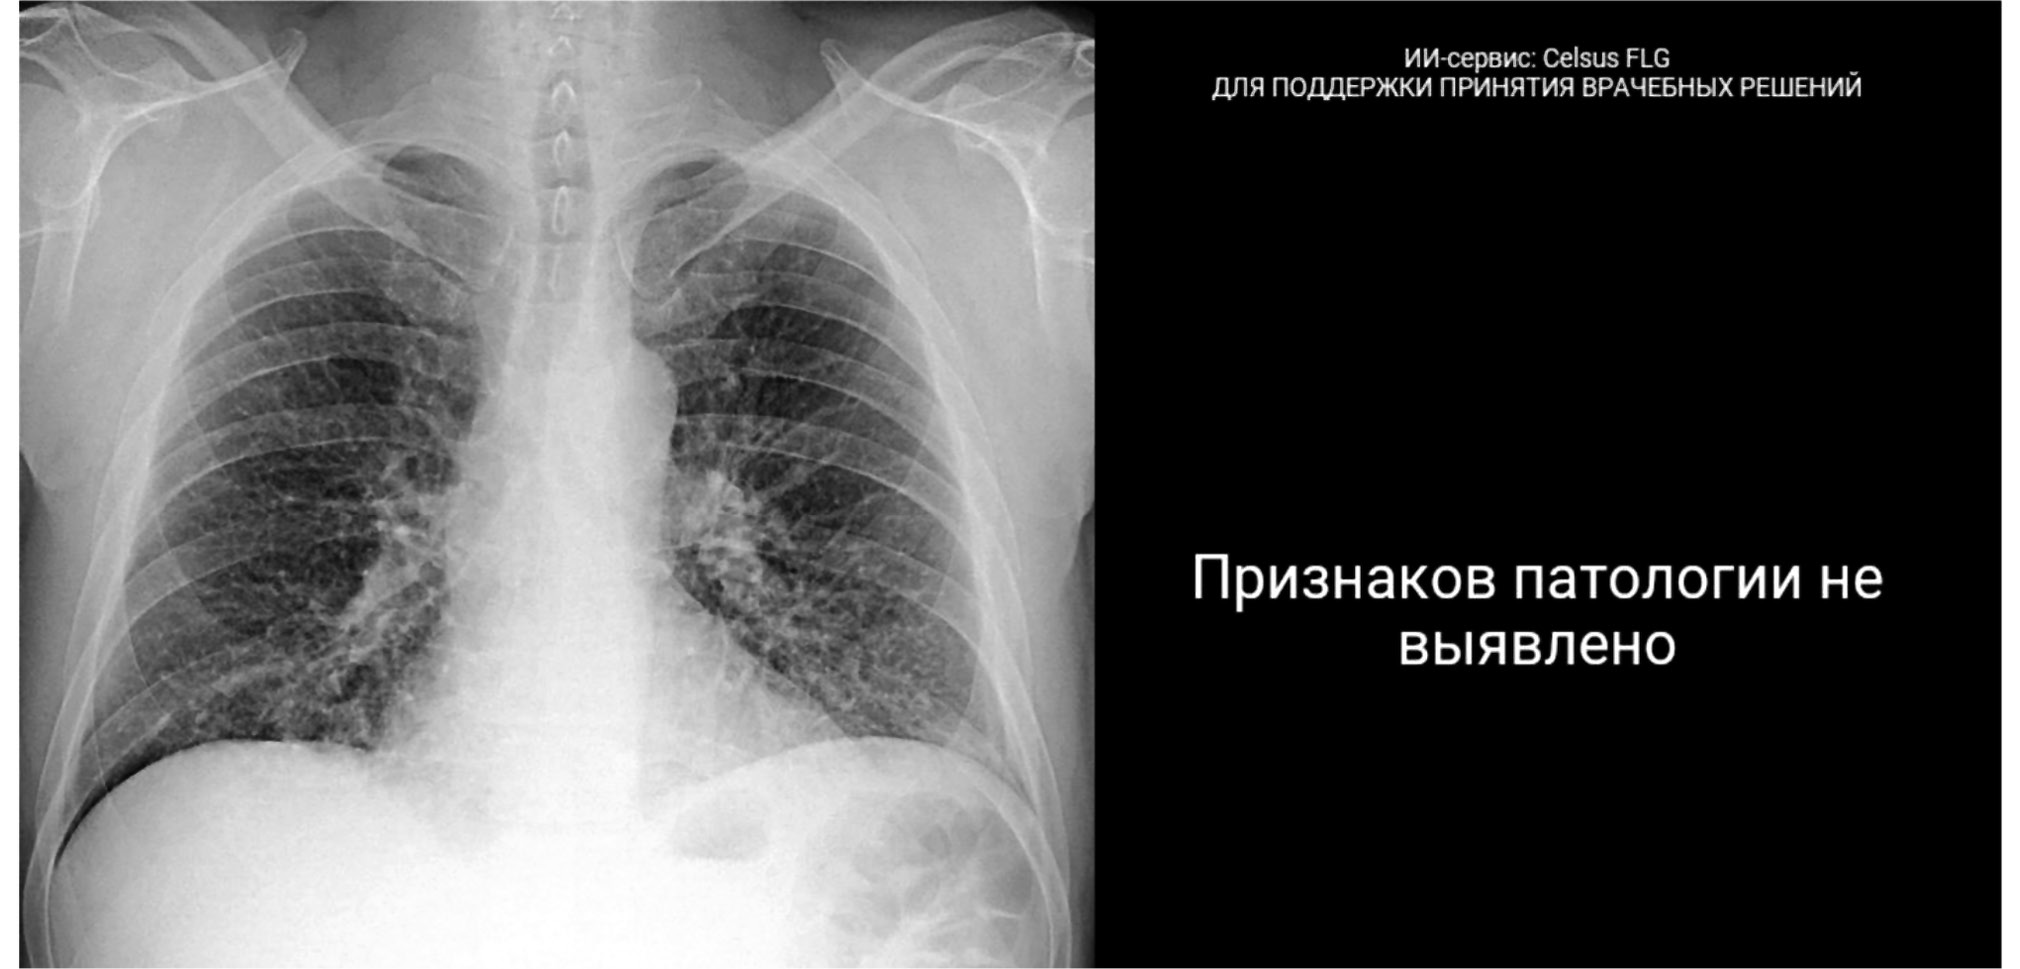

Рис. 2. Пример отображения результатов работы сервиса искусственного интеллекта в электронной карте пациента в Единой медицинской информационно-аналитической системе г. Москвы: автоматически сформированное заключение об отсутствии патологических отклонений в формате электронной медицинской записи.